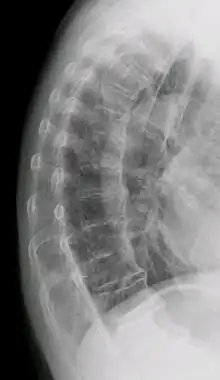

| DISH in an 80 year old female, also with T11 fracture. | |

Diffuse idiopathic skeletal hyperostosis (DISH) is a condition characterized by abnormal calcification/bone formation (hyperostosis) of the soft tissues surrounding the joints of the spine, and also of the peripheral or appendicular skeleton.[1] In the spine, there is bone formation along the anterior longitudinal ligament and sometimes the posterior longitudinal ligament, which may lead to partial or complete fusion of adjacent vertebrae. The facet and sacroiliac joints tend to be uninvolved. The thoracic spine is the most common level involved.[2] In the peripheral skeleton, DISH manifests as a calcific enthesopathy, with pathologic bone formation at sites where ligaments and tendons attach to bone.

DISH is diagnosed by findings on x-ray studies. Radiographs of the spine will show abnormal bone formation (ossification) along the anterior spinal ligament. The disc spaces, facet and sacroiliac joints remain unaffected. Diagnosis requires confluent ossification of at least four contiguous vertebral bodies.[2] Classically, advanced disease may have "melted candle wax" appearance along the spine on radiographic studies.[13] In some cases, DISH may be manifested as ossification, or enthesis, in other parts of the skeleton.